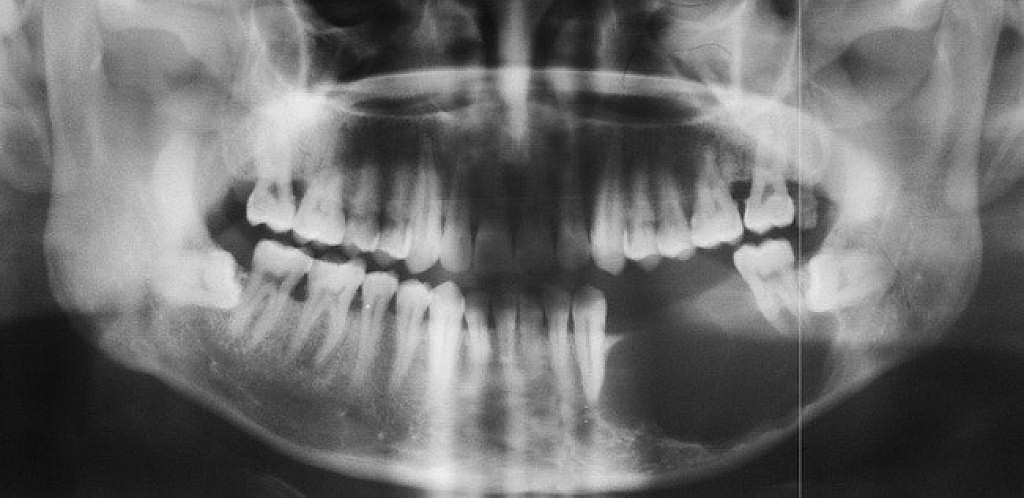

Ameloblastoma is a rare odontogenic tumor, which means it's formed from the normal tissues found in the mouth. Their location is predominately the lower jaw, also known as the mandible. Still, they can be found in the upper jaw or maxilla as well. Sometimes, ameloblastomas are located in the soft tissues surrounding the jaws. There is no known cause for this kind of tumor. However, it may be associated with impacted third molars. Ameloblastomas are usually noncancerous (benign), and they generally affect people between 40 and 60 years old.

Ameloblastoma Symptoms and Diagnosis

Ameloblastoma is usually painless, with the only symptom being swelling in the area. It is usually only identified on radiographic examination in a dental office. Early developing lesions do not displace teeth or cause numbness, so the patient may not know a tumor is growing in one of their jawbones. If a potential lesion is identified on a dental radiograph, more elaborate imaging is required. This will include a CAT scan and possibly an MRI. However, the diagnosis cannot be solely determined by imaging. It requires a biopsy to make the final diagnosis. Cysts will sometimes appear similar to the ameloblastoma on the imaging.

Some ameloblastomas are known to have malignant variants that are difficult to control locally. Metastases may occur, usually in the lung, but can spread through lymph nodes to other organs.